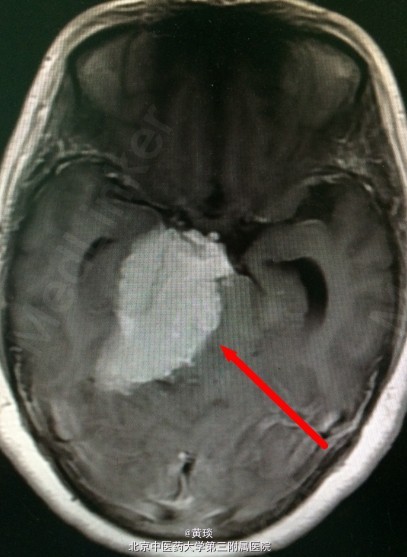

头颅MRI提示:桥小脑角区巨大脑膜瘤

诊断:脑膜瘤 处理:开颅切除

脑膜瘤长这么大的确实不多见,患者是一个农村妇女,家庭条件不太好,不到最后迫不得已轻易不进医院。这个手术不容易,做了足足有5个小时。